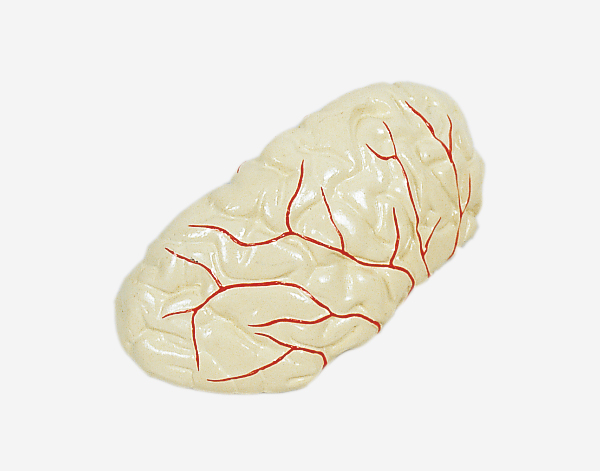

Human Brain With Arteries

Model of Human Brain With Arteries

This model facilitates the medical students to get a correct understanding of the external features of the brain and its arte

rial supply as a whole,as well as the relations between their component portions.External features of the brain:cerebral

hemisphere,brain stem,cerebellum.The arterial supply of the bra inaources,vertebral,internal carotid arteries,arteria supply of the

cerebellum and cerebrum.Made of PVC and can be separated into 7parts,on base.Size(cm):17x17x13